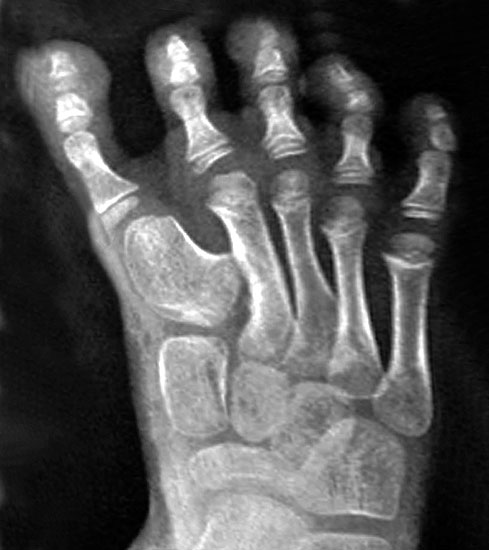

Hallux varus congenitus

Ein besonderes Krankheitsbild stellt der Hallux varus congenitus dar. Es ist eine sehr selten beobachtete angeborene skelettäre Medialdeviation des 1. Metatarsophalangealgelenkes und der Großzehe 21.

Sie ist häufig vergesellschaftet mit einer Polydaktylie, mitunter mit einem Brachymetatarsale I, mit einer Duplikation der Knochen der medialen Säule, von der distalen Phalanx bis zum Os naviculare reichend, bzw. mit einer systemischen Erkrankung (Corte-Real, 1997; Vispo-Seara, 1998; De Valentine, 1995; Tachdijan, 1990), 812.

Prinzipiell werden 3 Typen unterschieden (Tachdijan M, 1990):

• alleiniger primärer Hallux varus

• Hallux varus assoziiert mit anderen Fußdeformitäten, z. B. Fehlen eines Se-sambeines oder dem kongenialen Klumpfuß

• Hallux varus assoziiert mit systemischen Deformitäten des Skelettes (Syndrome).

Bei einer gedoppelten 1. Zehe bei einer präaxialen Polydaktylie ist eine Varusstellung typisch (Hefti, 1998).

Die Fehlstellung beim Hallux varus congenitus ist häufig sehr ausgeprägt.

Angeborene Deformität und Fehlanlage 1. Strahl (eigenes Bildmaterial) (Vispo-Seara 1998, Hefti 1998)

Abbildung 9

Mit zunehmendem Wachstum und Alter wird die Abweichung der Großzehe zunehmend symptomatisch. Es können keine normalen Schuhe getragen werden, es entstehen kosmetisch schwerwiegende Probleme. Deshalb wird zu einer frühzeitigen Korrektur im Säuglings- und Kleinkindalter geraten 12, d. h. im 9. – 24 Lebensmonat 215.

Die Therapie ist immer operativ, wobei sich der individuelle Eingriff an der jeweiligen Dysplasie orientiert.

Gute Erfolge zeigen die Entfernung akzessorischer Knochen (Mc Elvenny, 1941; Corte-Real, 1998), sowie eine iatrogene Syndaktylie zwischen der 1. und 2. Zehe.

Möglich sind weiterhin subkapitale Osteotomien des Metatarsale I sowie eine auf- klappende Osteotomie am Os cuneiforme mediale (Hefti, 1998) mit K-Draht-Fixation oder die 1958 von Farmer 5 beschriebene Technik mit ausgeführter Lappentechnik (de Valentine, 1992).

Sinn jeglicher Prozedur ist das Schaffen eines reorientierten belastungsfähigen Fußes, welcher schmerzfreies Gehen ermöglicht. Eine Rezidivneigung besteht bei allen Gelenk erhaltenden Operationen am Vorfuß.